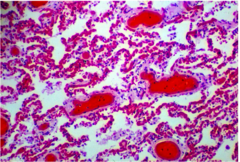

Alveolar

-In little sacs or nests -Nested structure

Reticular

-Resembling a network or netlike array -Microcystic or honeycomb appearance